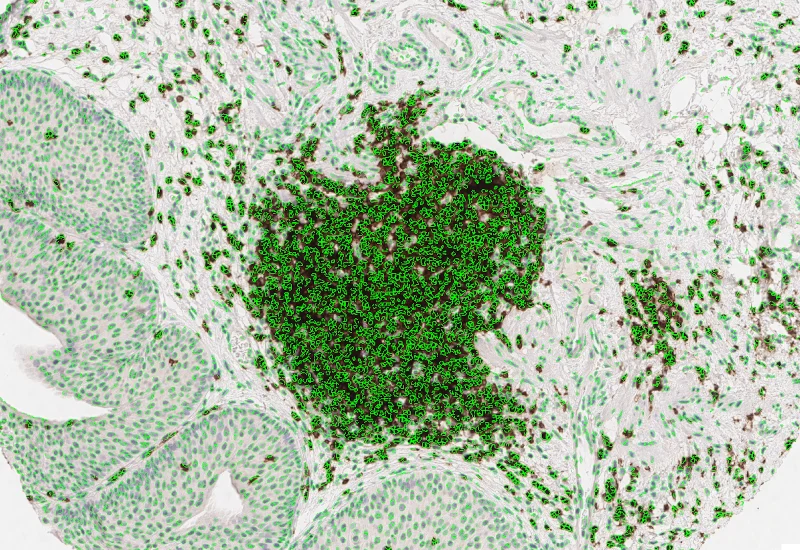

Nuclei detection

Proximity map lymphoid cluster